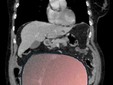

Per mesi la gigantesca cisti ovarica, con un diametro di circa 28 centimetri, è rimasta nascosta, senza dare segnali evidenti. La paziente non si era accorta di nulla. L’allarme è scattato quando la massa, associata alla presenza di una seconda neoplasia intestinale, ha iniziato a comprimere il colon, provocando sintomi acuti ed improvvisi fino ad una grave difficoltà intestinale non più ignorabile.

Fondamentale in questa fase il contributo della Radiologia dell'ospedale Sant’Anna, che fornisce l’imaging preoperatorio indispensabile per affrontare un quadro clinico di eccezionale complessità.

Durante l’intervento emerge tutta la gravità della situazione. La gigantesca neoplasia ovarica viene asportata: pesa circa 6 chilogrammi, con un volume paragonabile a quello di una gravidanza gemellare a termine. Ma non è l’unica minaccia. I sintomi più pericolosi sono legati alla sofferenza intestinale, che richiede un intervento immediato e coordinato di più specialisti.